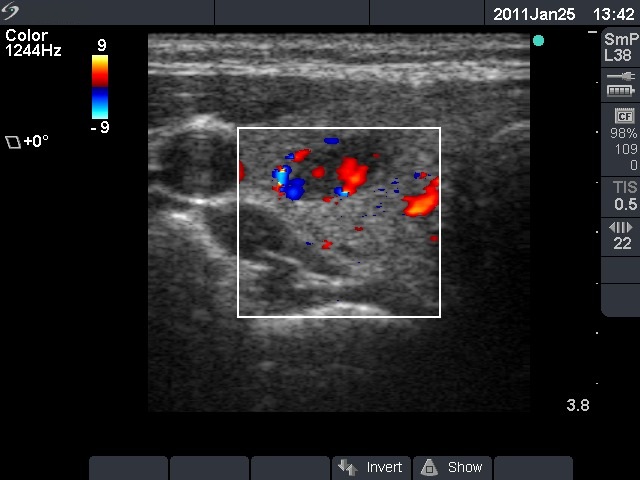

Ultrasonography: a hypoechogenic nodule with a type 3 vascular pattern in the right lobe.